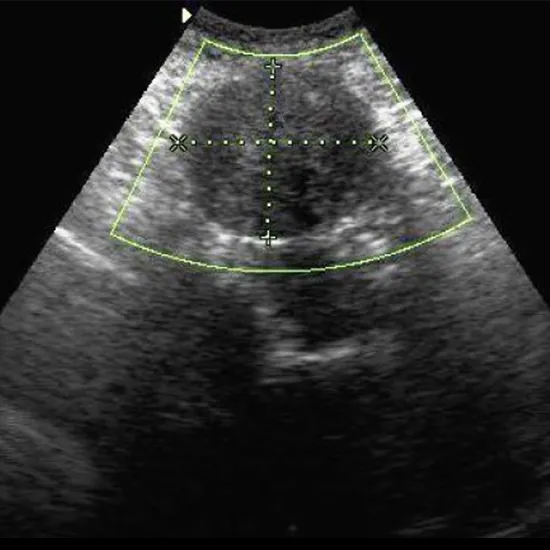

Whole Abdominal Ultrasound (USG) is a type of imaging test using high-frequency sound waves to create images of an abdomen (belly). It is used to view organs in the abdomen, including the liver, gallbladder, kidney, spleen, and pancreas. It can also help us examine how some of the blood vessels in this area work.

The USG whole abdomen test procedure will be performed while lying down. The skin around the abdomen is treated with a transparent, water-based conductive gel. The abdomen is next probed using a handheld tool known as a transducer. The test can take up to 30 minutes in most cases.

Ultrasound whole abdomen or whole abdomen ultrasonography is a painless, rapid, non-invasive and safe technique that is used for the examination of abdominal contents such as liver, gall bladder, pancreas, spleen, intestine, kidneys as well as abdominal blood vessels.